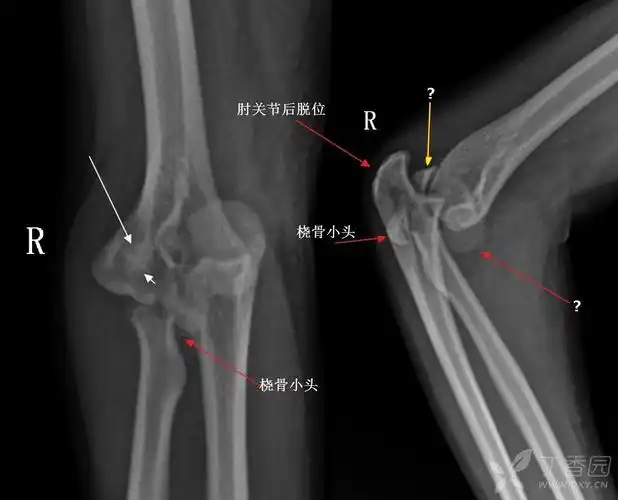

肱骨内,外髁及鹰